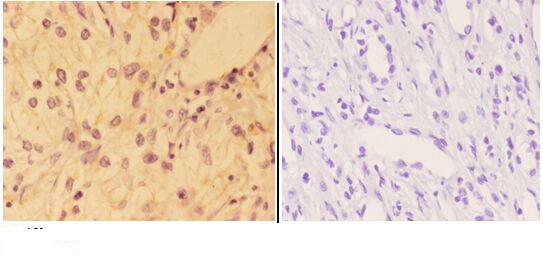

Expressed in prostate cancer and levels increase from the normal to the malignant state (at protein level). Expressed in all human cell types so far analyzed. The Tyr-176 phosphorylated form shows a significant increase in expression in breast cancers during the progressive stages i.e. normal to hyperplasia (ADH), ductal carcinoma in situ (DCIS), invasive ductal carcinoma (IDC) and lymph node metastatic (LNMM) stages.